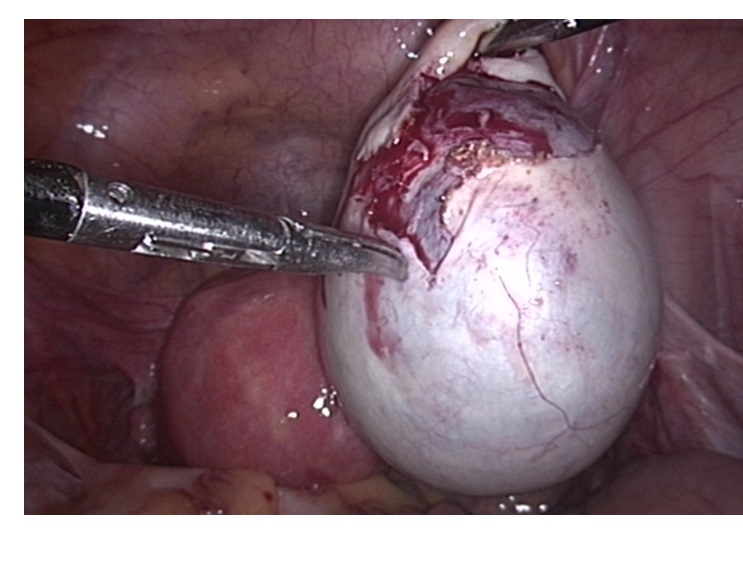

妇科开展:腹腔镜子宫肌瘤剔除术、子宫切除术、卵巢肿瘤切除术、宫颈癌根治术、卵巢癌减灭术,输卵管微整形术,宫腔镜检查及电切术,并开展钬激光治疗(全国领先),无脱垂大子宫肌瘤患者的阴式子宫切除术(省内领先)等先进技术。